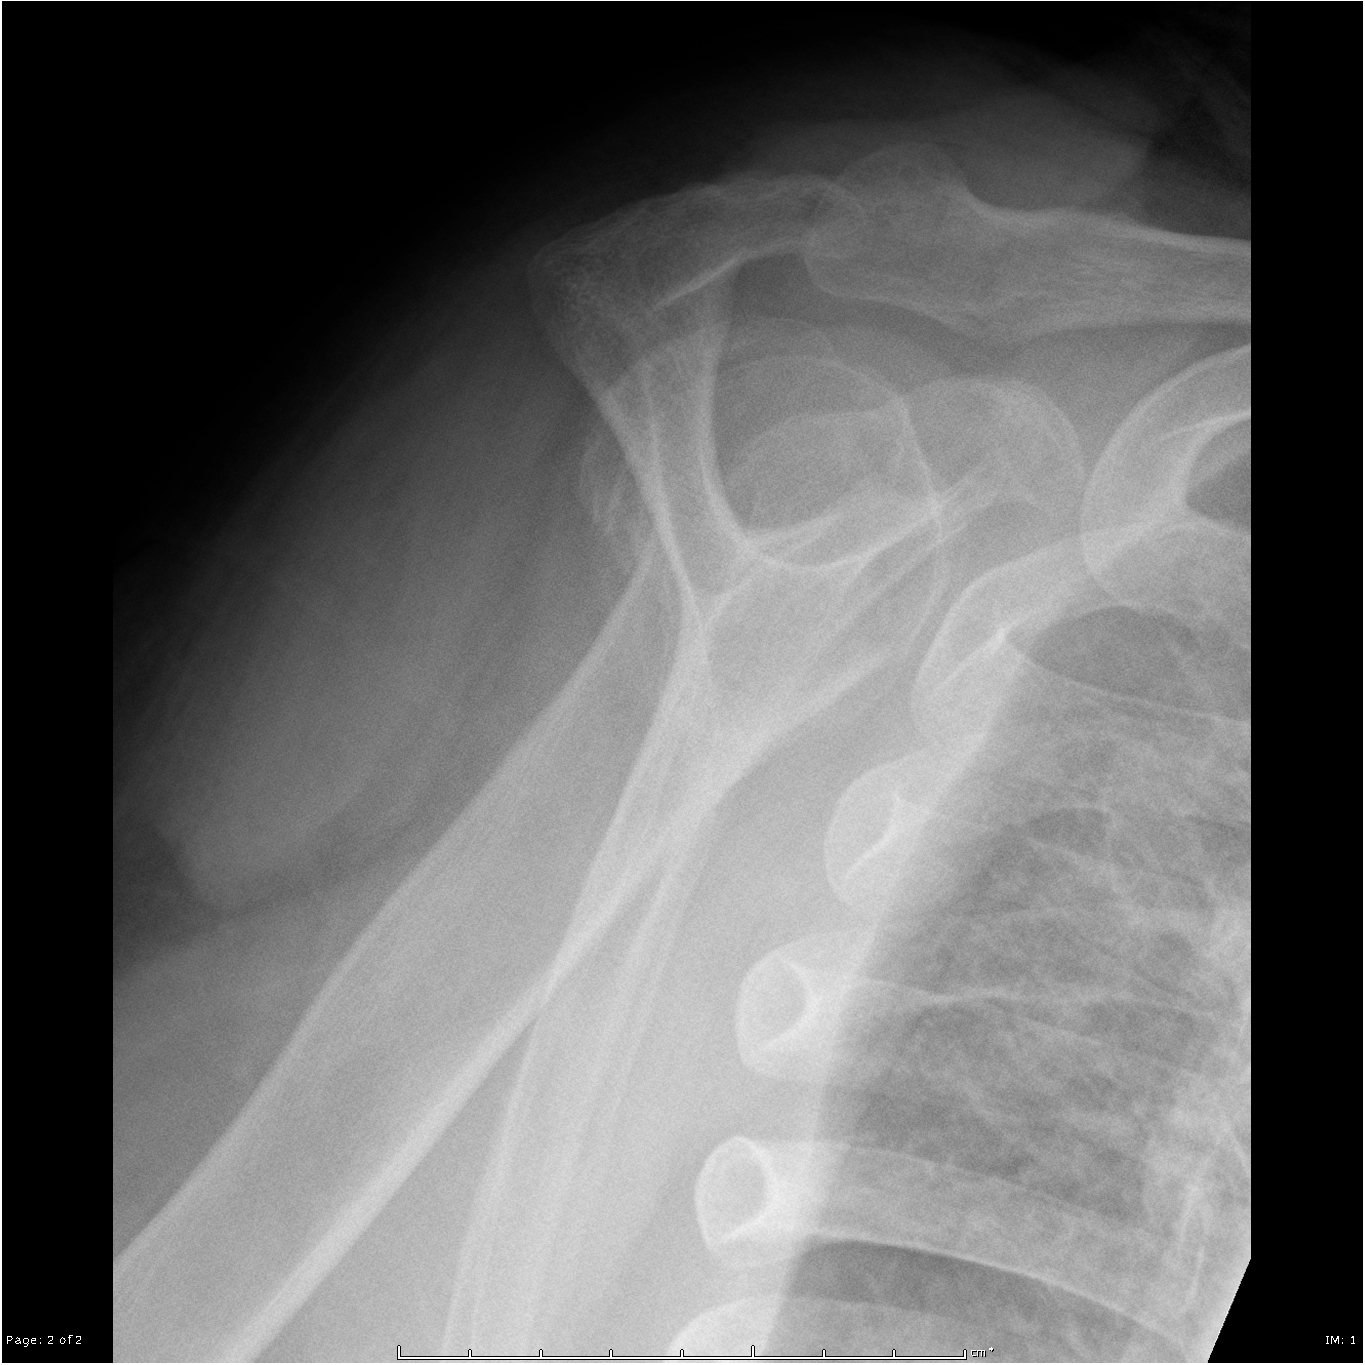

Beschreiben Sie die Befunde auf dem vorliegenden Röntgenbild der Schulter.